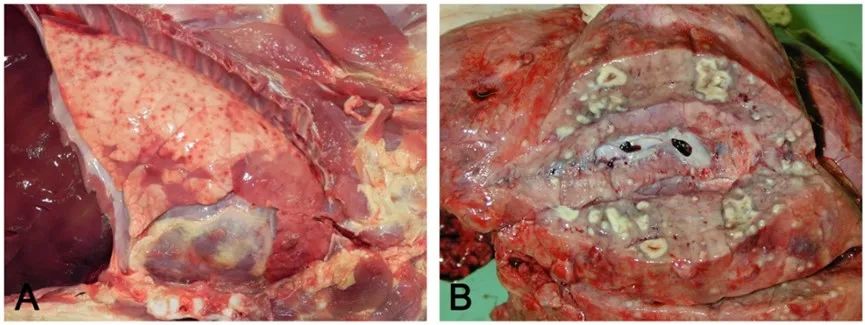

(A)急性充血/出血病灶,通常与肠道的菌血症有关。(B)化脓灶被正常肺实质包围,由于肺外化脓性静脉炎引起的微血栓所致。